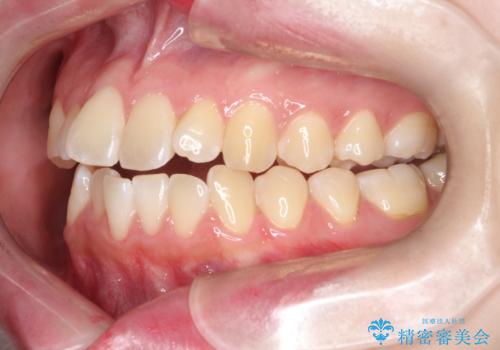

【インビザライン】オープンバイト。凸凹を治したい

- オープンバイトを主訴に来院されました。

インビザラインを用いIPRと遠心移動を行いオープンバイトと叢生の改善を行なっております。

前歯の叢生がわずかにありますが、追加アライナーの作成は希望されなかったため、歯を動かしていく動的治療は終了となりました。